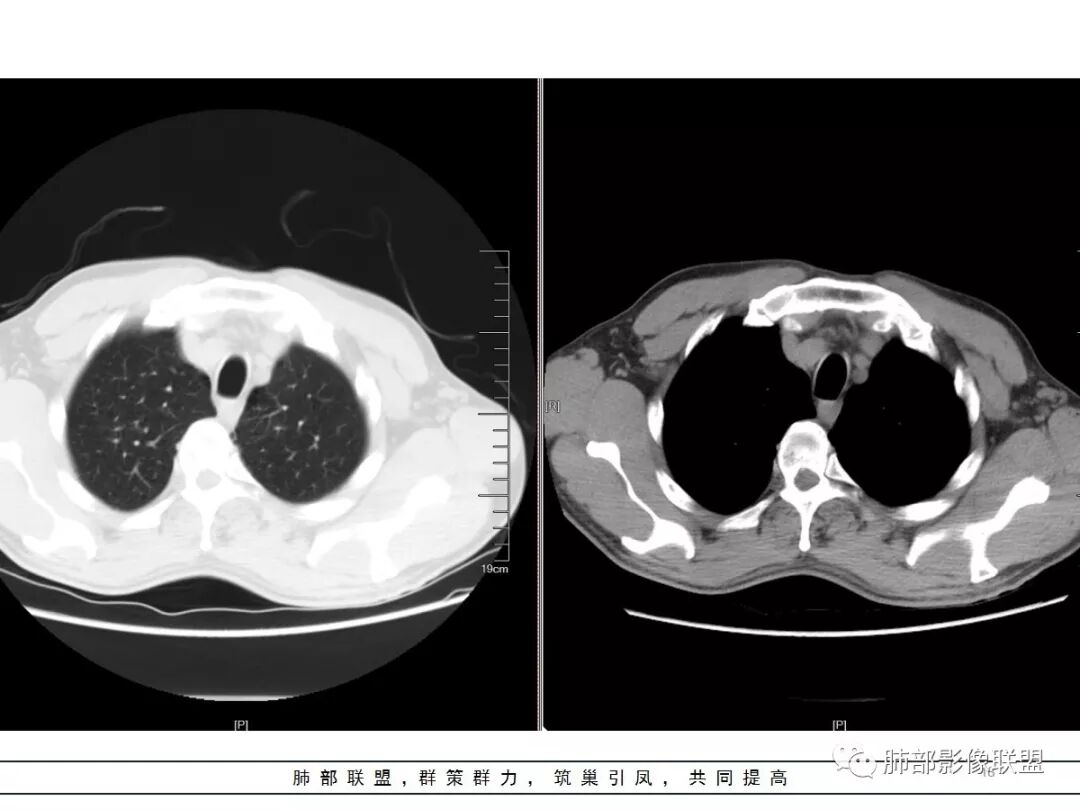

男,57岁,因“体检发现右上肺占位”入院。凝血常规、血常规、肾功能等均未见明显异常。

CT值:

平扫  18                          动脉期  28                      静脉期 41

重建